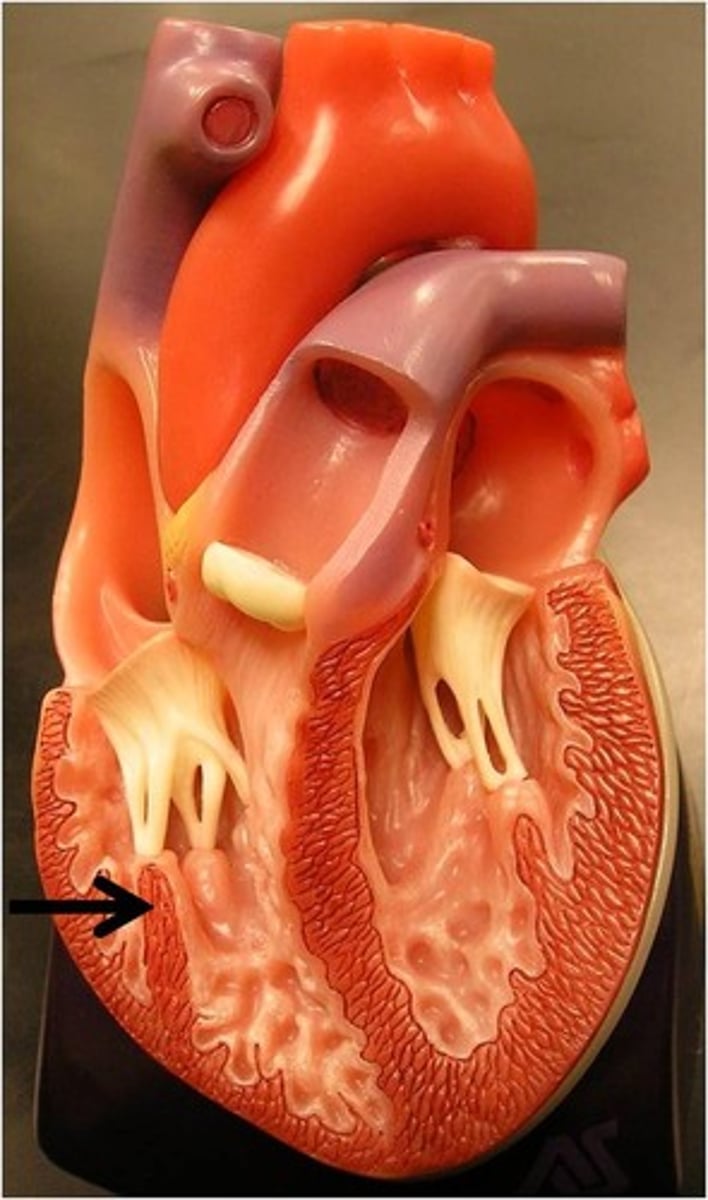

Trabeculae carneae

Ridged wall of the ventricles (contracts)

Papillary muscles

Have chordae tendineae that are attached to the valve flaps so they don't prolapse